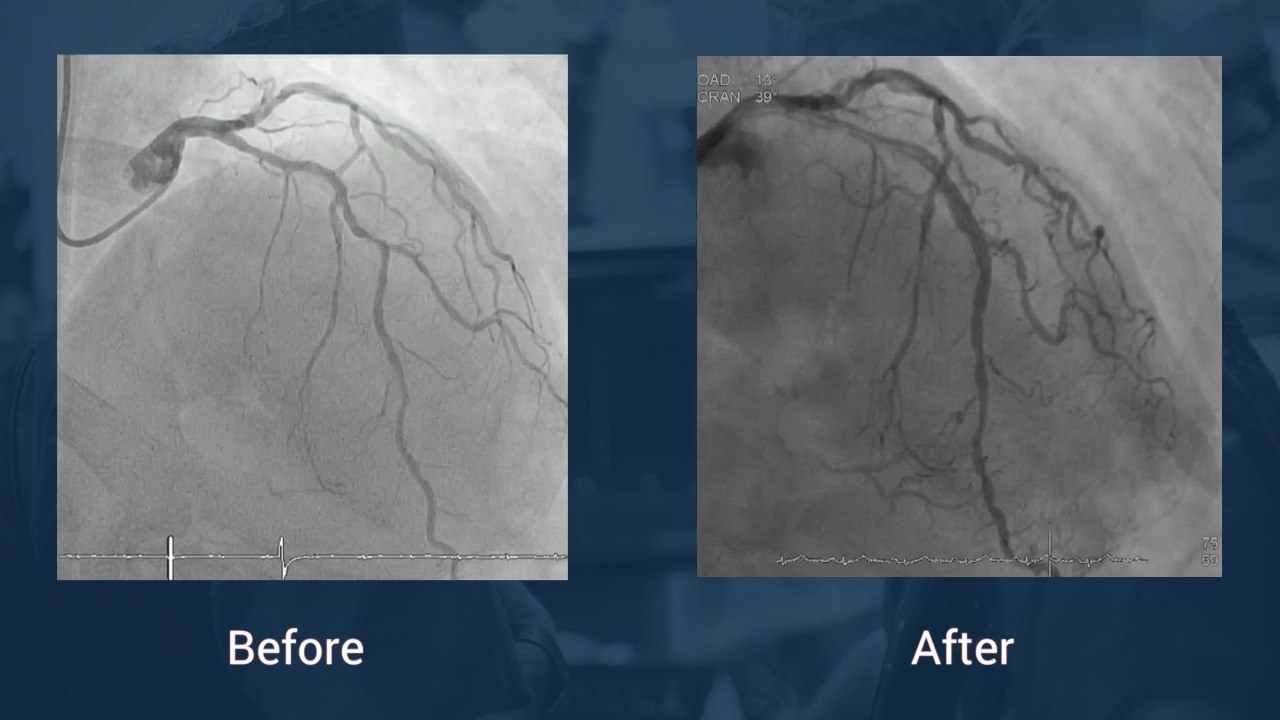

Highly calcified LAD

Rotablation followed by Cutting balloon - Dr Serra, Dr Jimenez, Dr Bajo & Dr Delgado